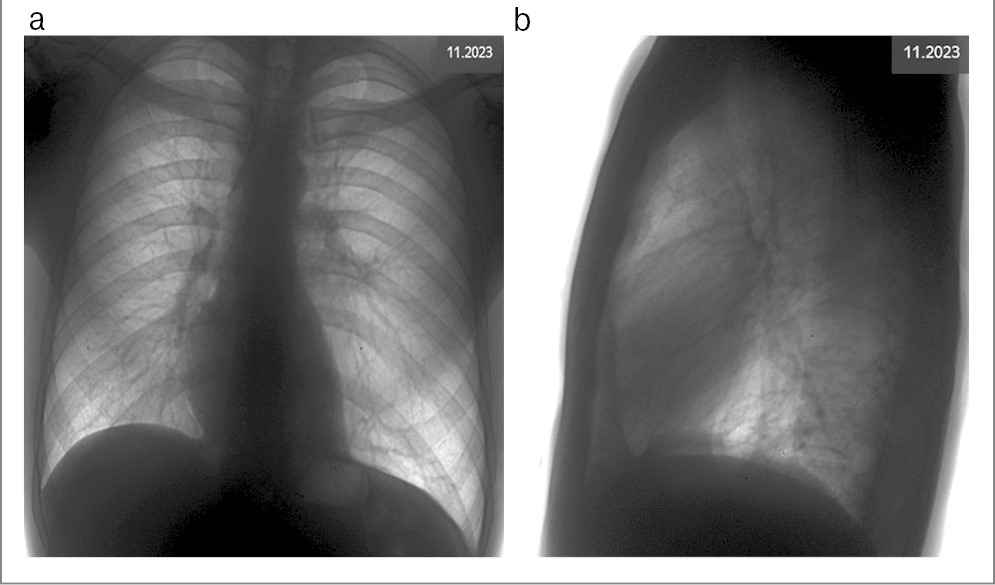

На представленной рентгенограмме ОГК, выполненной на предыдущем этапе лечения в ноябре 2023 г., инфильтративных изменений легочной ткани не выявлено. Левое легкое визуально больше в объеме. Отмечается участок повышенной воздушности легочной ткани в базальных отделах слева за счет измененного (обедненного) сосудистого рисунка (по сравнению с правыми отделами), смещение тени сердца вправо (рис. 1).

Рис. 1. Рентгенограмма ОГК в двух проекциях.

Определяется: a – левое легкое больше в объеме, участок ограниченного просветления легочной ткани в базальных отделах слева за счет повышенной воздушности легочной ткани (по сравнению с правыми отделами), смещение тени сердца вправо, купол диафрагмы слева косонисходящий; b – на уровне тела Th11 позвонка визуализируются 3 округлых участка высокой плотности с четкими ровными контурами – ортогонально расположенные сосуды.